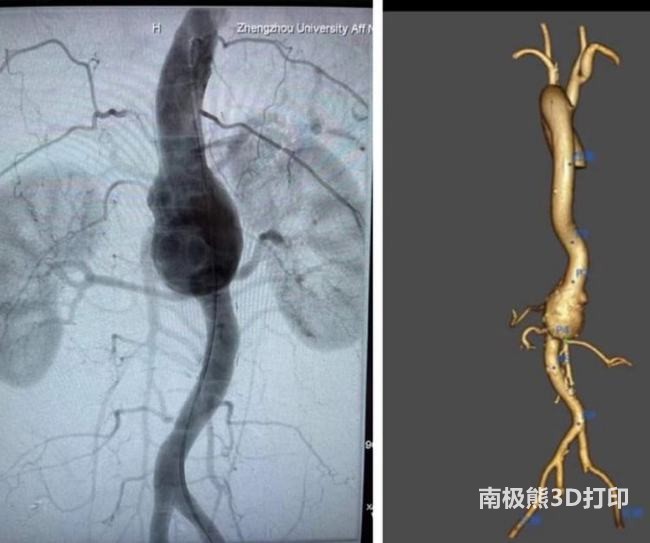

the patient recovered well after the operation. A 50-year-old male patient was admitted to the hospital with the main complaint of “abdominal pain for more than 1 month”. CTA in another hospital showed: abdominal aortic aneurysm-like dilatation, involving the celiac trunk artery, superior mesenteric artery and both renal arteries.

Aortic aneurysms or aortic dissections involving visceral arteries have always been difficult to treat. Traditional surgical open surgery is extremely challenging, with huge trauma, high complications and high mortality. Although endovascular aortic repair is the mainstream treatment for aortic disease, it is minimally invasive and has few complications, but pure endovascular treatment (fenestration stent or branch stent technique) involving visceral arteries is a very complicated technical operation. To accurately measure the shape of the aneurysm and the location of the openings of various important branches, extremely high surgical skills are also required during the operation. In this patient with abdominal aortic aneurysm involving the splanchnic artery, the3D printing(Print out the vascular lesion model), in vitro fenestration, accurately locate the four branches of the visceral arteries and the fenestration position of the blood vessels, and successfully completed the operation.